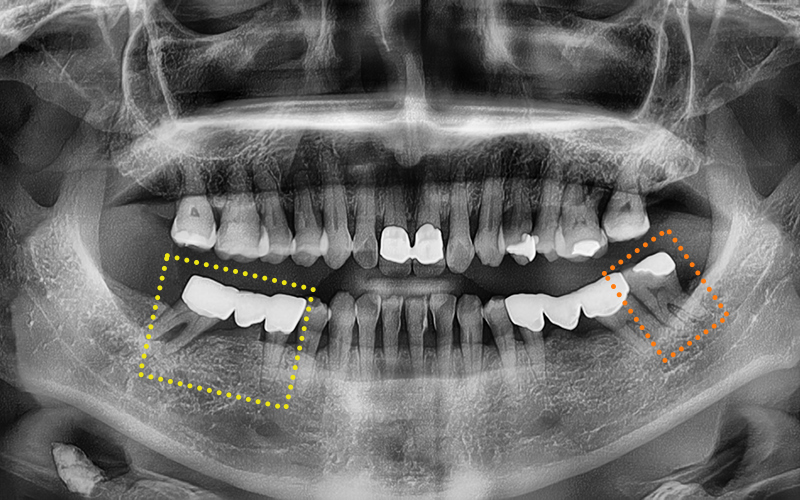

She was experiencing pain in the lower molars on both sides,

and we took a panoramic X-ray

to check the situation in detail.

🔍 Treatment plan and process

At Seoul Ob Dental Hospital,

we carefully planned treatment

while considering the patient’s age,

overall health, and treatment burden.

🦷 Final plan

✔ Lower left wisdom tooth

ㅡ> Immediate extraction due to signs of infection

✔ Existing bridge on the lower right

ㅡ> Plan for removal, extraction, and implant placement